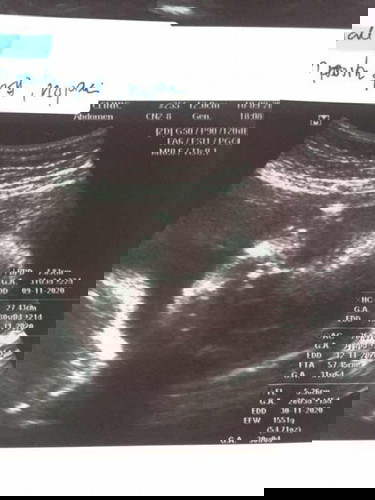

ซาวด์ภาพขาวดำปกติ 600 บาทค่ะ แต่คุณหมอให้ภาพซาวด์4มิติแถมมาให้ด้วยค่ะ รวมยาด้วยก็ประมาณ1000+บาท

ซาวที่กรุงเทพ 1500 กลับไปซาวที่กาญ 500 แต่อยากว่าล่ะราคาต่างกันความละเอียดก็ต่างกัน555

400-600 ค่ะ ซาวธรรมดา+ 4 มิติ +รวมยาบำรุง คะ จะได้ซาวแบบนี้ทุกเดือนค่ะ

ถ้าเป็นซาวด์ขาว-ดำ พร้อมยาบำรุง 600 บาท แต่ถ้าซาวด์4มิติ 1,000 บาท

2-3-4มิติสามอย่าง รอบละ1,000-1,500จ้า ไม่รวมยาบำรุง

ครั้งละ 800 +ยาบำรุง +ซาวธรรมดา ของทุกๆเดือน

บ้านนี้ซาว4ครั้ง ครั้งละ1870รวมยาบำรุง

อัลตร้าซาวด์ธรรมดา ไม่เอายา500-600ค่ะ